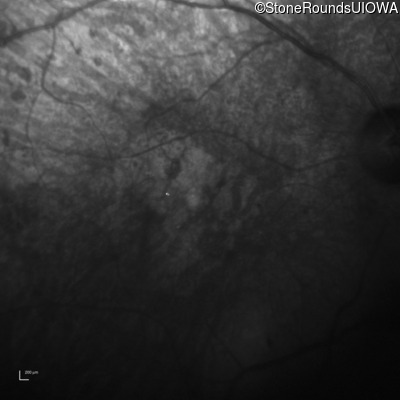

Infrared Fundus Photograph - Right - Hand Motion 1' sc

Exemplar